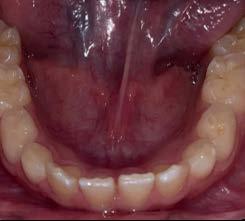

Entre los elementos que conforman al sistema estomatognático, están los dientes caninos, órganos dentales esenciales en la fisiología masticatoria; punto de unión y continuidad estética entre la línea de la sonrisa y el corredor posterior del arco dental, además de que ejercen la función de pilares estabilizadores en la oclusión fisiológica (Figura 1).

Los caninos son indispensables durante los movimientos de lateralidad y vitales para la continuidad de los arcos dentales, tanto en la dentición decidua como en la permanente; son responsables del funcionamiento y la armonía oclusal. Su posición adecuada en el arco asegura un buen contorno de la cara, sonrisa agradable y armónica con la estética facial. (Figura 2).

El canino divide su cara vestibular en 2 vertientes, una mesial que se continúa con los incisivos y otra distal que se alinea con los dientes posteriores, razón por la cual su ausencia genera alteraciones muy importantes en la oclusión y la estabilidad fisiológica del sistema estomatognático (Figura 3).